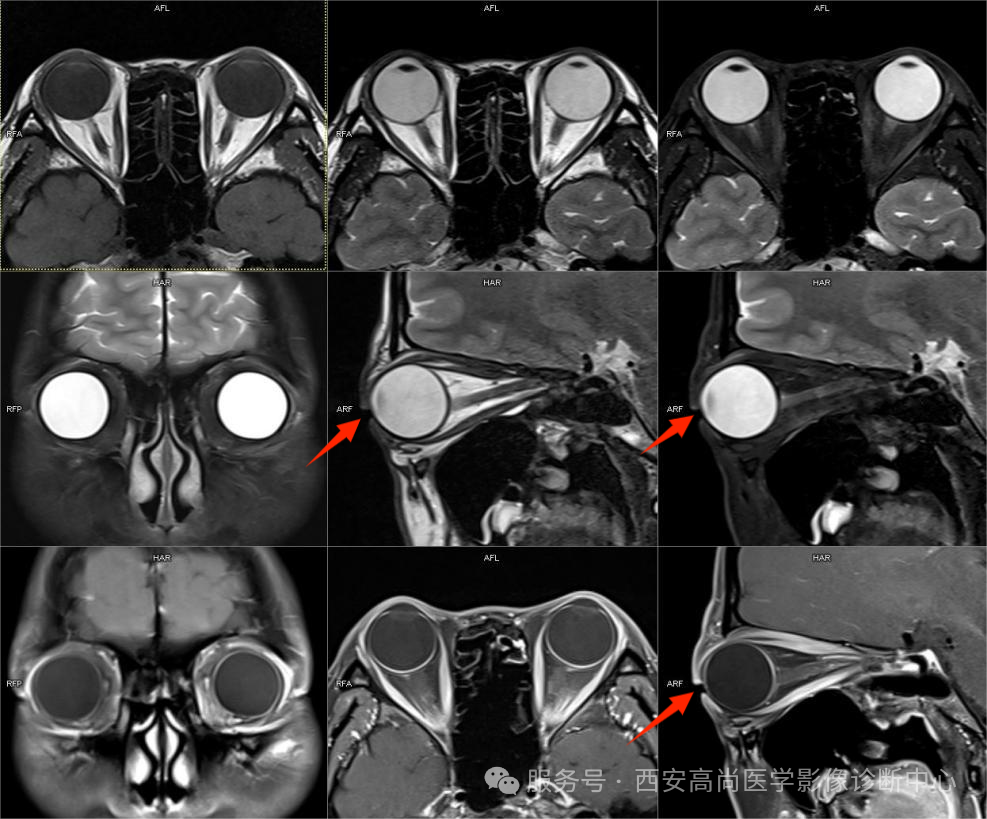

外伤-义眼

右眶内义眼植入术后,眶上壁骨质结构欠连续,前结膜区可见新月形双低信号,右眼睑及眶周皮下软组织压脂信号稍增高,部分呈网格状改变,局部呈弱强化影。